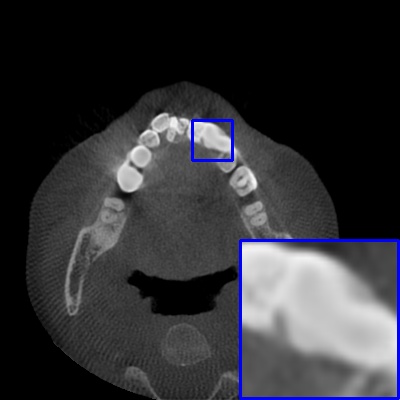

Figure 4: Comparison of MAR images by different methods on real-world MA image. The last image is the metal mask by selecting the pixel area over 2800HU in the MA image.

Results on real-world MAR. We also compare these methods on dental CBCT images with real-world metal artifacts. The visual results on one sample are shown in Fig. 4. We observe that our MARformer-T and MARformer-L well seperate the adjacent teeth and retain their shapes. This shows that our MARformers, though trained on synthetic data, are effective on real-world MAR.